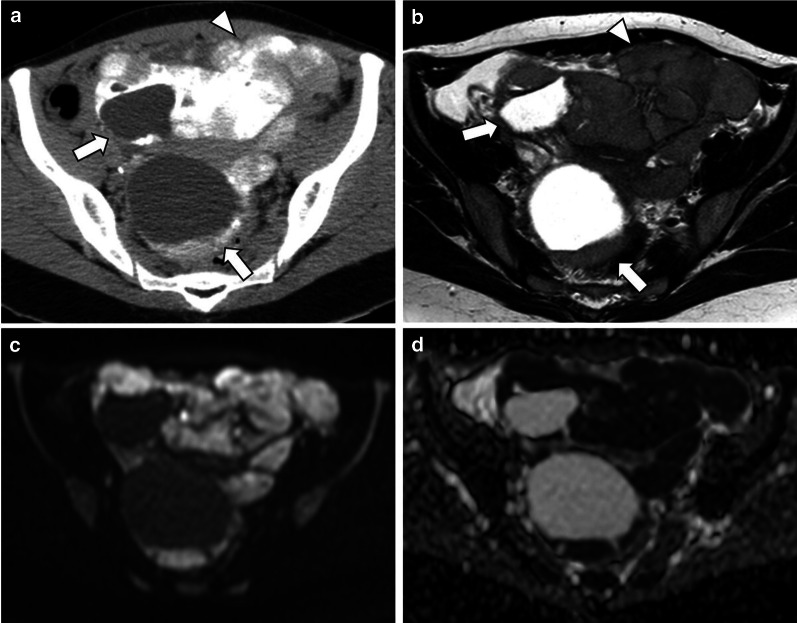

Fig. 5.

Bilateral LGSC in a 28-year-old female. Coronal and axial enhanced CT images (a, b) display a bilateral multicystic tumour with thick septa and parietal nodules with multiple psammoma bodies (arrows). Enhanced CT image (c), 3 years after cytoreductive surgery, reveals peritoneal metastases on the hepatic surface and in subhepatic space with exuberant calcified psammoma bodies (arrows)

Fig. 6.

Bilateral LGSC with foci of SBT with peritoneal metastases in a 48-year-old female. Coronal and axial unenhanced CT images (a, b) display a pelvic bilateral cystic tumour (arrows) with several calcified psammoma bodies and calcified peritoneal metastases, namely in the hepatic surface and in the right hypochondrium peritoneum (arrowheads). Severe ascites is also seen, which is a rare manifestation in this type of tumour. Axial T2-weighted MR image (c) demonstrates metastases adherent to the liver surface (arrowheads)